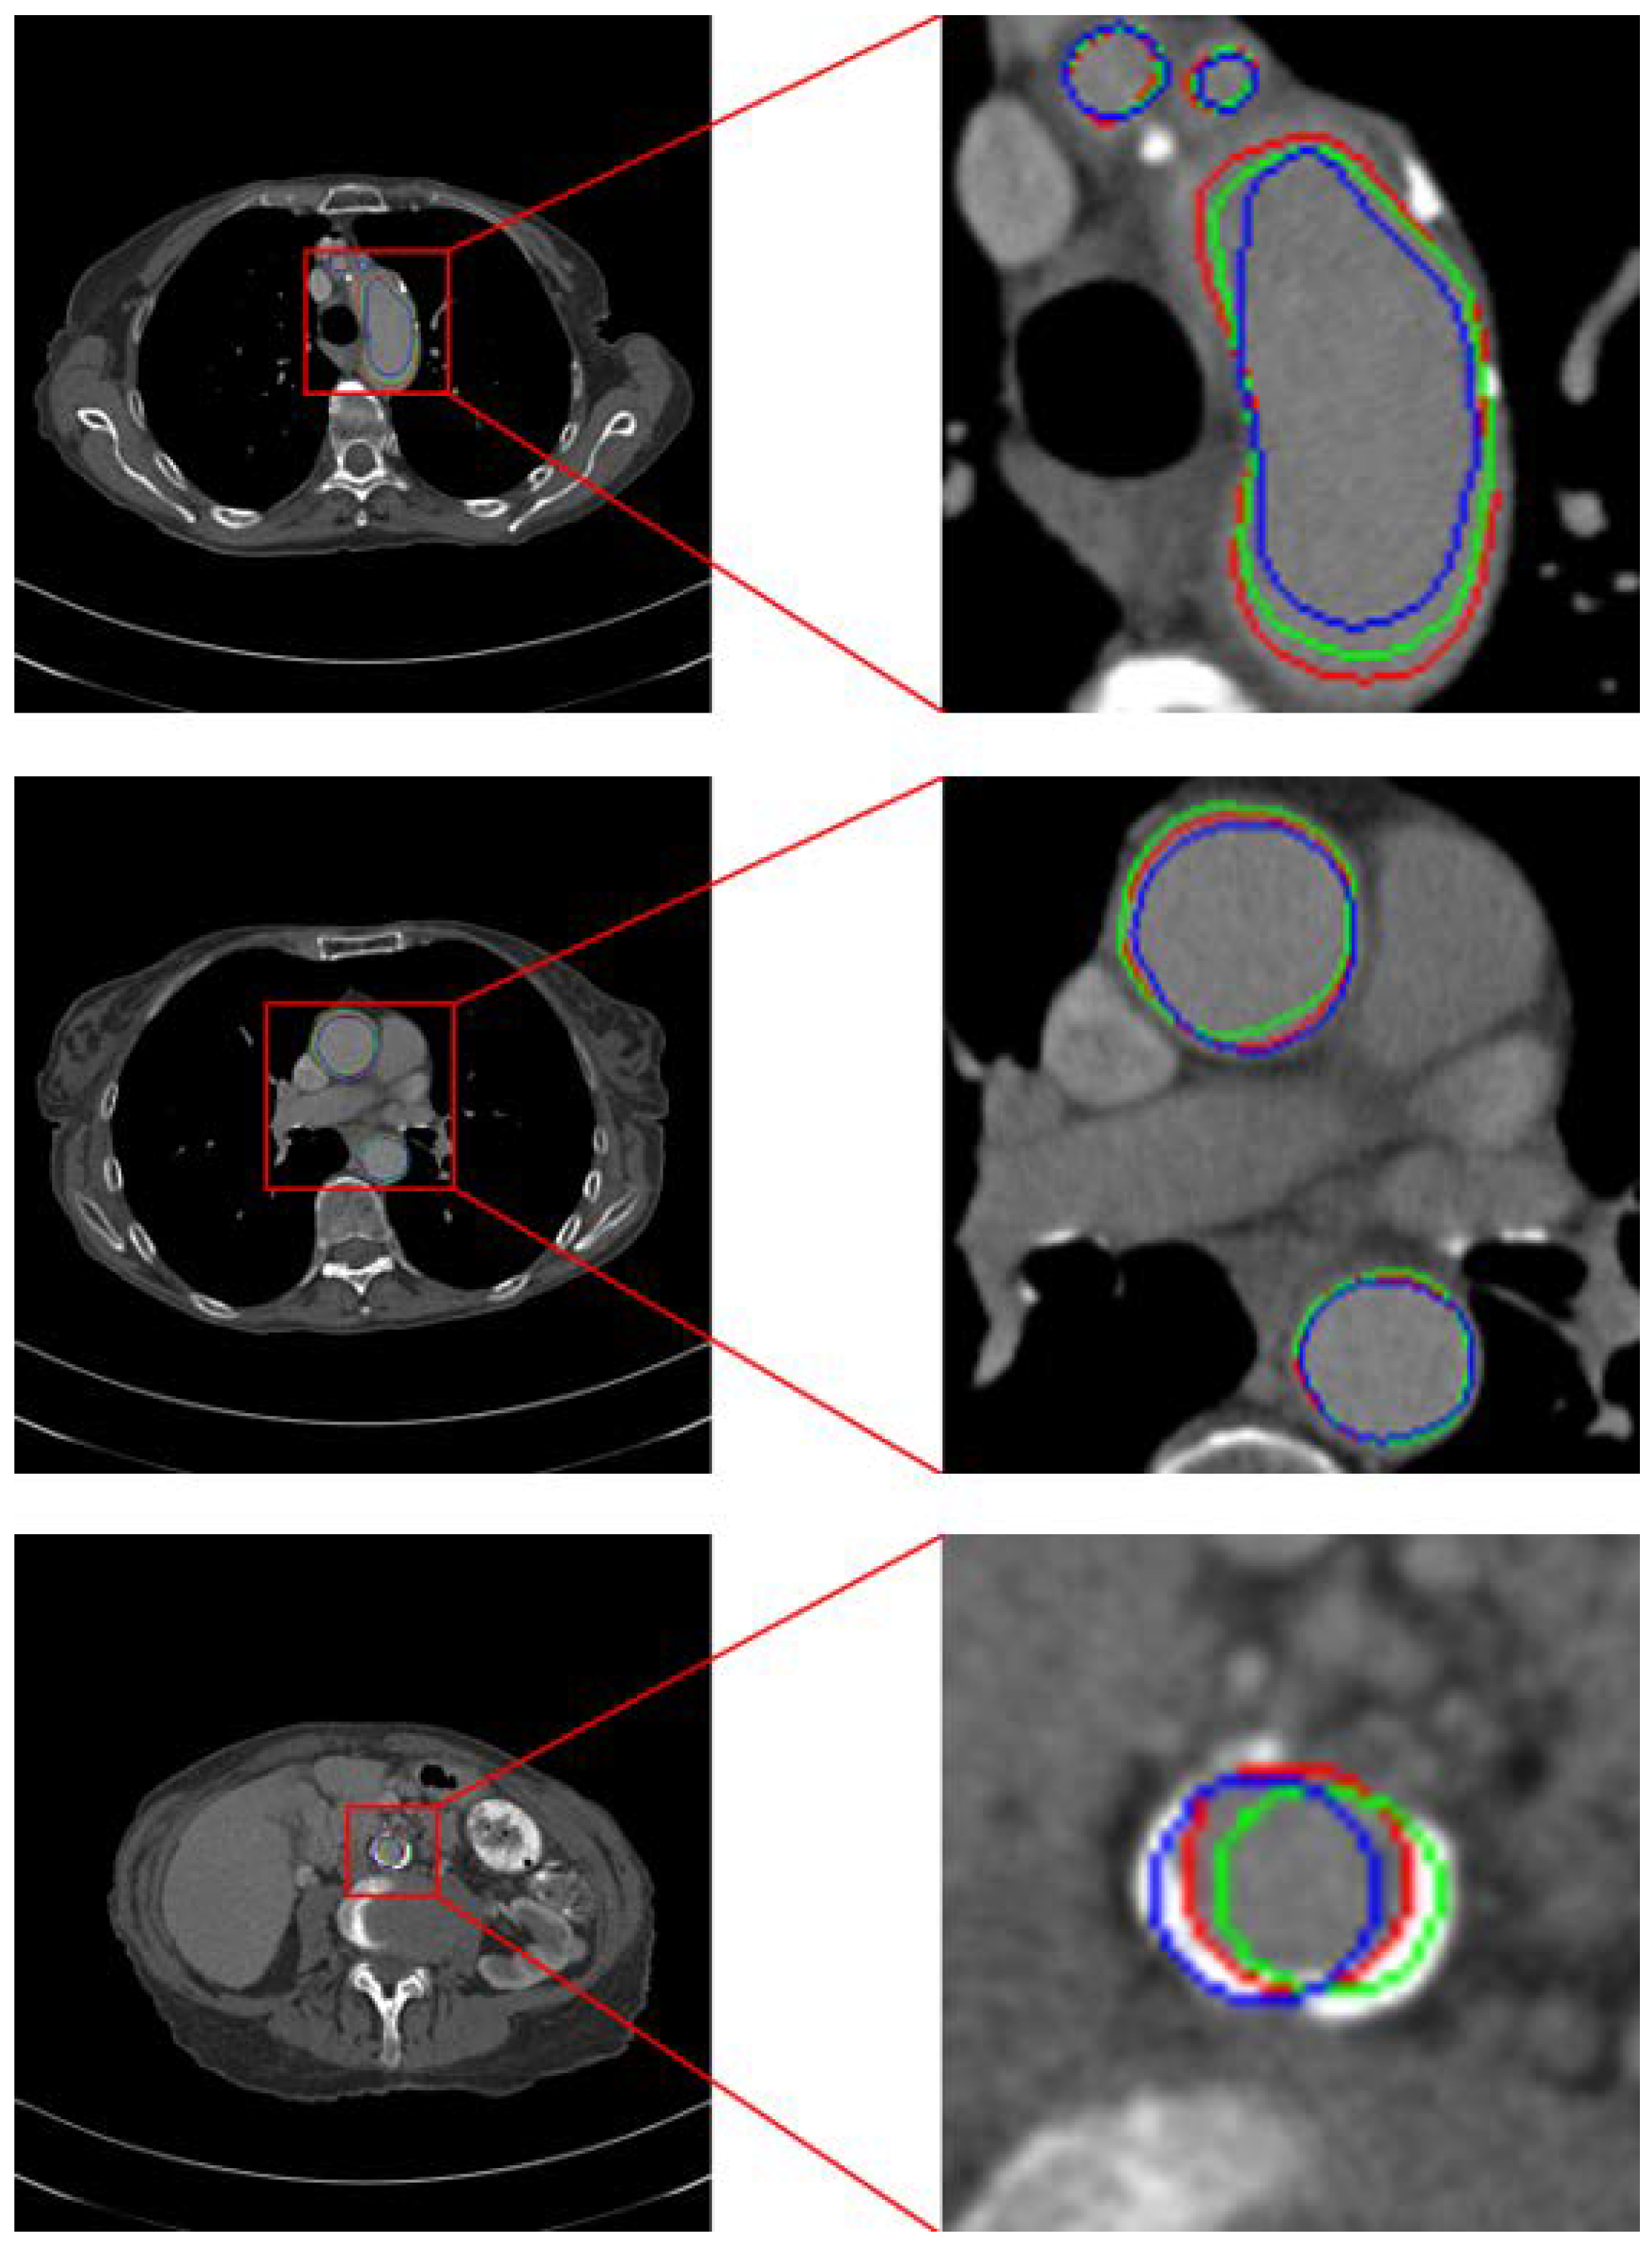

Therefore, we adopt a hard attention-type gating scheme to improve model performance. As shown in Figure 3, the aorta typically exhibits only minor positional shifts and generally similar morphology in adjacent CT slices. Leveraging this property, we generate an enhancement map using the previous slice’s prediction to guide the current slice. Nevertheless, small inter-slice differences remain, and the aorta’s positional offset varies across cases as a function of slice thickness. To increase the likelihood that the enhancement region covers the entire aorta despite these shifts, we expand the region using the strategy illustrated in Figure 4.

Figure 3. Location of aorta in CT images with similar serial numbers. The green circle is the location of the aorta in the previous CT image, the blue circle is its location in the next CT image, and the red circle indicates the location of the aorta in the central CT image.